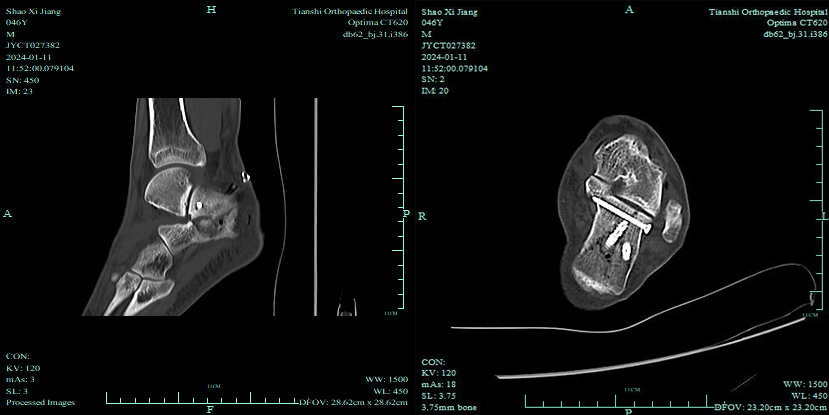

跟骨骨折可分为关节外骨折和关节内骨折。其中关节内骨折的CT分型有多种方法,最常用的是Sanders分型,其分型以冠状面及矢状面CT扫描为基础,分为4型。方法为选择后距下关节的最大面,用A、B两线由外向内将距骨面3等分,则跟骨被对应的A、B两线分为3部分,即内侧柱、中柱和外侧柱,C线对应距骨面内侧缘,A线对应外侧缘。

Ⅲ型:后关节面出现2根骨折线,并根据其部位分AB、BC以及AC三个亚型,各亚型均有一中央凹陷骨折段。

Ⅳ型:包括那些严重的粉碎性骨折,后关节面出现4个骨折块。

SandersⅡ型、SandersⅢ型及SandersⅣ型常需采取外科手术复位治疗,对严重的凹陷性骨折区必要时还需做植骨术辅助治疗。

5、有效地降低软组织并发症,术后患者功能恢复更快。适用于SandersII型及部分简单的SandersIII型骨折。特别是Ⅱa、Ⅱb、Ⅲab型。